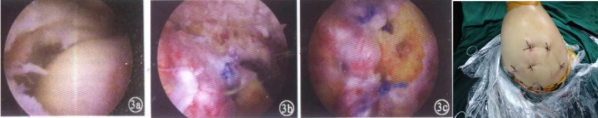

(3)小切口联合关节镜:

该种手术适用于非巨大撕裂损伤患者,治疗方式对三角肌损伤较小,最大程度地保留三角肌功能,创伤小,有利于术后早期康复和训练。